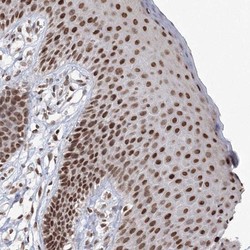

- Immunohistochemistry-Paraffin: C3orf33 Antibody [NBP1-90874] - Staining of human vulva/anal skin shows strong nuclear positivity in squamous epithelial cells.